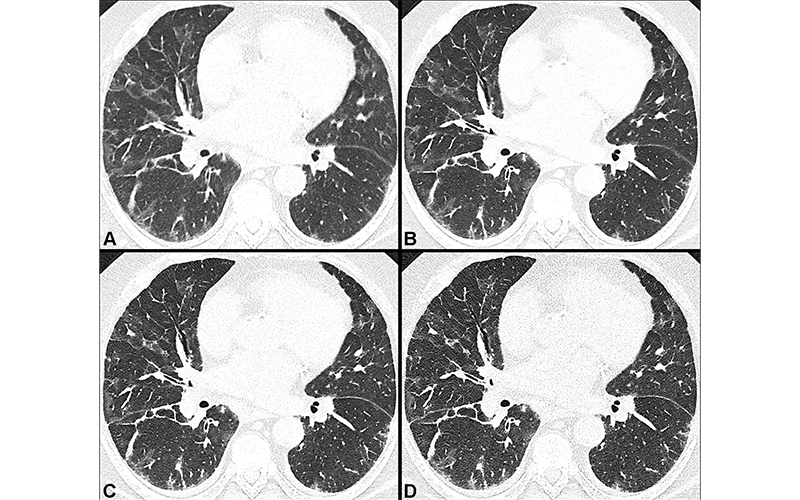

New CT technology outperforms conventional CT in detecting subtle damage in the lungs of patients with persistent symptoms of COVID-19, according to a new study published in Radiology. The technology could lead the way to earlier treatment and better outcomes for the growing number of people with COVID-related lung damage, researchers said.

Dr. Heidinger and colleagues studied PCD CT’s potential as a method for imaging the lungs of people with persistent symptoms after COVID-19. They compared PCD CT with conventional CT in 20 adults, mean age 54 years. The participants had one or more COVID-19-related persisting symptoms, such as cough and fatigue.

Conventional CT showed post-COVID-19 lung abnormalities in 15 of 20 (75%) participants. PCD CT revealed additional lung abnormalities in half of the participants. The most common abnormality found by PCD CT was bronchiolectasis, damage to the airways that can cause difficulties in clearing mucus from the lungs.

“In our study investigating lung abnormalities in symptomatic post-COVID patients, we were able to detect subtle lung abnormalities in 10 of 20 participants using PCD CT that were not seen in conventional CT,” Dr. Heidinger said. “Moreover, PCD CT has potential in decreasing radiation dose and in artifact reduction, representing direct benefits to patients.”

PCD CT’s ability to detect these subtle lung abnormalities is especially important, Dr. Heidinger said, because patients with persistent symptoms following COVID-19 can develop irreversible lung damage known as lung fibrosis. Conventional CT is one of the primary methods for detecting and diagnosing lung fibrosis, but it can miss the subtle abnormalities indicative of early-stage fibrosis.